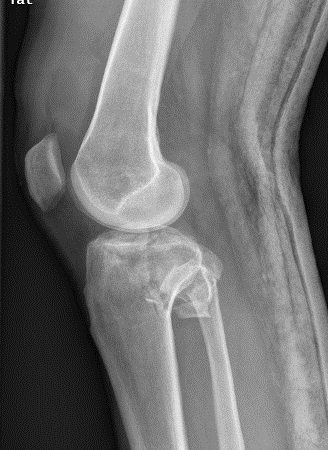

1、图1-2 术前X片见骨折似乎不是特别严重

胫骨平台骨折的病人,如果在30年前大多数医院应该会选择保守治疗。那时CT尚未普及,而仅凭X片会低估其损伤的严重程度,容易产生可不必手术的假象,也难以准确判断骨折移位情况。即使想做手术,也没有什么好的内固定可供选用。